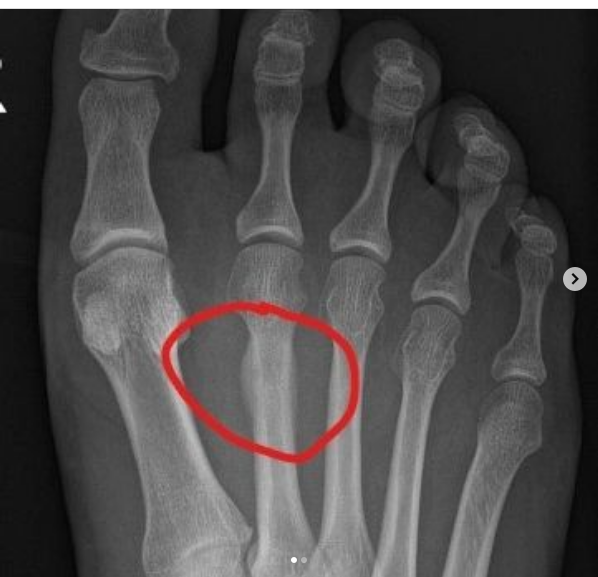

Lamentablemente, debido a una fractura por estrés, Eliya ha tenido que retirarse de la carrera. Estamos muy tristes, ya que Eliya era nuestro primer participante de Israel.

La carrera X-Pyr ha estado en mi punto de mira desde que empecé a volar. Es una carrera cumbre para los atletas de Hike& Fly. He pensado y entrenado mucho para preparar este monumental esfuerzo de atravesar los Pirineos con un trozo de nylon y dos piernas. Pero como suele ocurrir con las cosas que perseguimos con ahínco, me excedí: unas cuantas sobredosis de entrenamiento de volumen en asfalto me jodieron el hueso metatarsiano. Es una mierda, pero es lo que hay. Ser hombre significa aceptar las decepciones, espabilarse y seguir adelante. Los Pirineos esperarán.